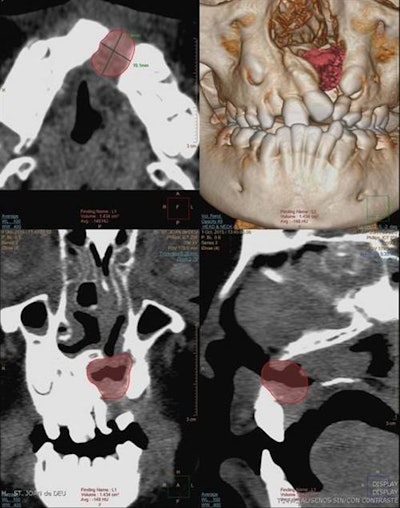

For alveolar bone graft planning, use CT with multiplanar reconstructions (MPR) and surface volumetric (3D), the authors recommended. For planar measurements, axial and coronal CT scans and volumetric measurements before bone grafting give a more accurate picture and help with surgical planning.

"Three-dimensional CT data is especially helpful in evaluating patients with severe craniofacial asymmetry, because they do not suffer from the magnification and distortion-related problems inherent in 2D projections," the authors wrote.

In the four- to six-month follow-up after alveolar bone grafting, the outcome checklist comprises assessment of bone bridge development (osseointegration), measurement of the bone volume of the graft on 3D CT, checking for the presence of oronasal fistula, and evaluation of facial symmetry. Reabsorption of the bone graft occurs mainly during the first postoperative three months and is closely related to long-term outcome, while normal resorption after one year can be up to 30% to 50% of the original graft volume.

When evaluating bone grafts with 3D CT, bone loss is more prominent in the bucco-palatine direction, and if resorption is higher than 50% or there is lack of normal eruption of adjacent teeth, graft failure should be suspected, according to Gómez-Chiari. Facial symmetry can be assessed by measuring the height from the pyriform aperture to the apex of the upper incisor in a coronal plane.